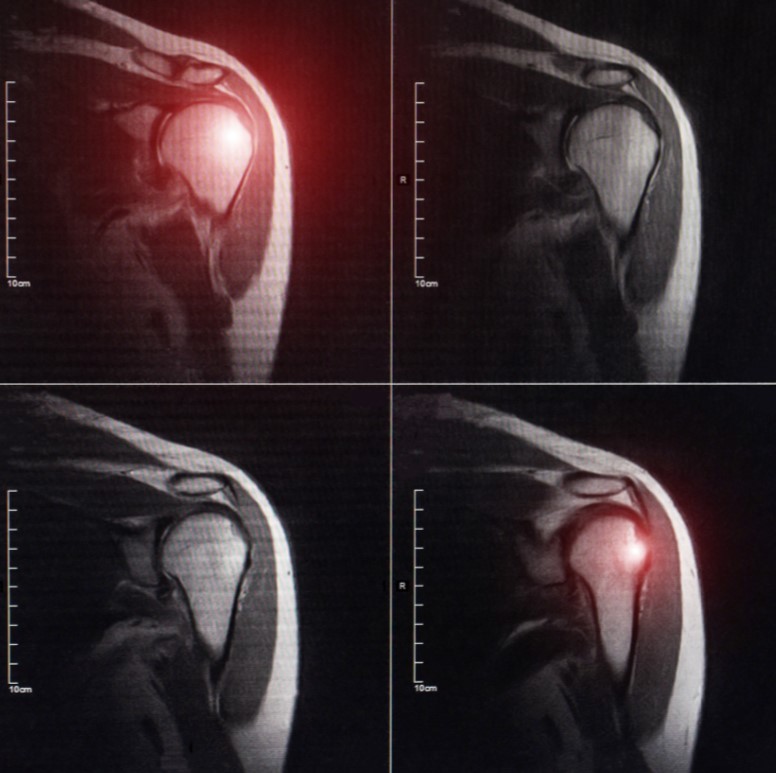

Frozen shoulder, or adhesive capsulitis as we doctors tend to refer to it, loosely describes the condition of stiff shoulder. Stiffness happens for a host of reasons but the two main types are:

Both types of frozen shoulder involve serious scarring and thickening of the typically elastic capsule tissue around the shoulder joint. Acquired frozen shoulder can be more complex and involve scarring of muscle layers and other tissue layers in the shoulder as well.